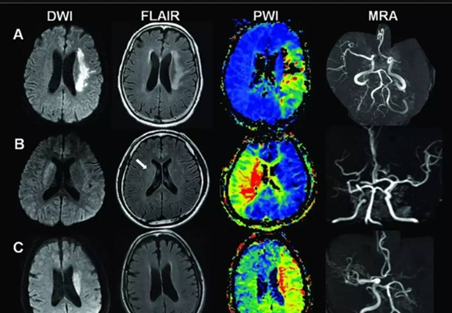

3、磁共振血管成像(MRA) 磁共振成像(MRI)通过无创成像方法,可动态观察血管的狭窄程度、斑块的体积大小及演变过程;对斑块成分及表面形态,包括纤维帽破裂和溃疡,加以分析,并对加速粥样病变进程的危险因子加以测评

图片